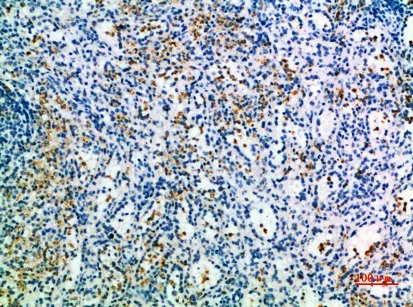

CD327 Rabbit Polyclonal Antibody

Cat: APRab08362